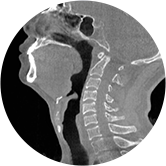

颈椎

腰椎

精准诊断

手术方案规划

术后随访